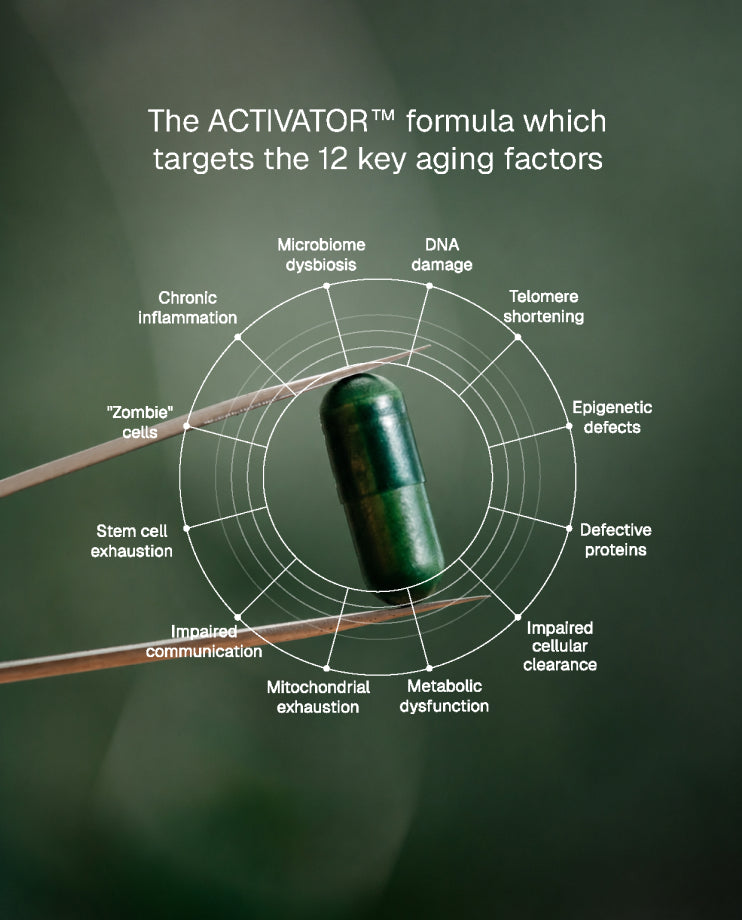

Our scientists have carefully selected ingredients that can highly affect the 12 hallmarks of aging and looked at how ingredients work together to amplify their effectiveness.